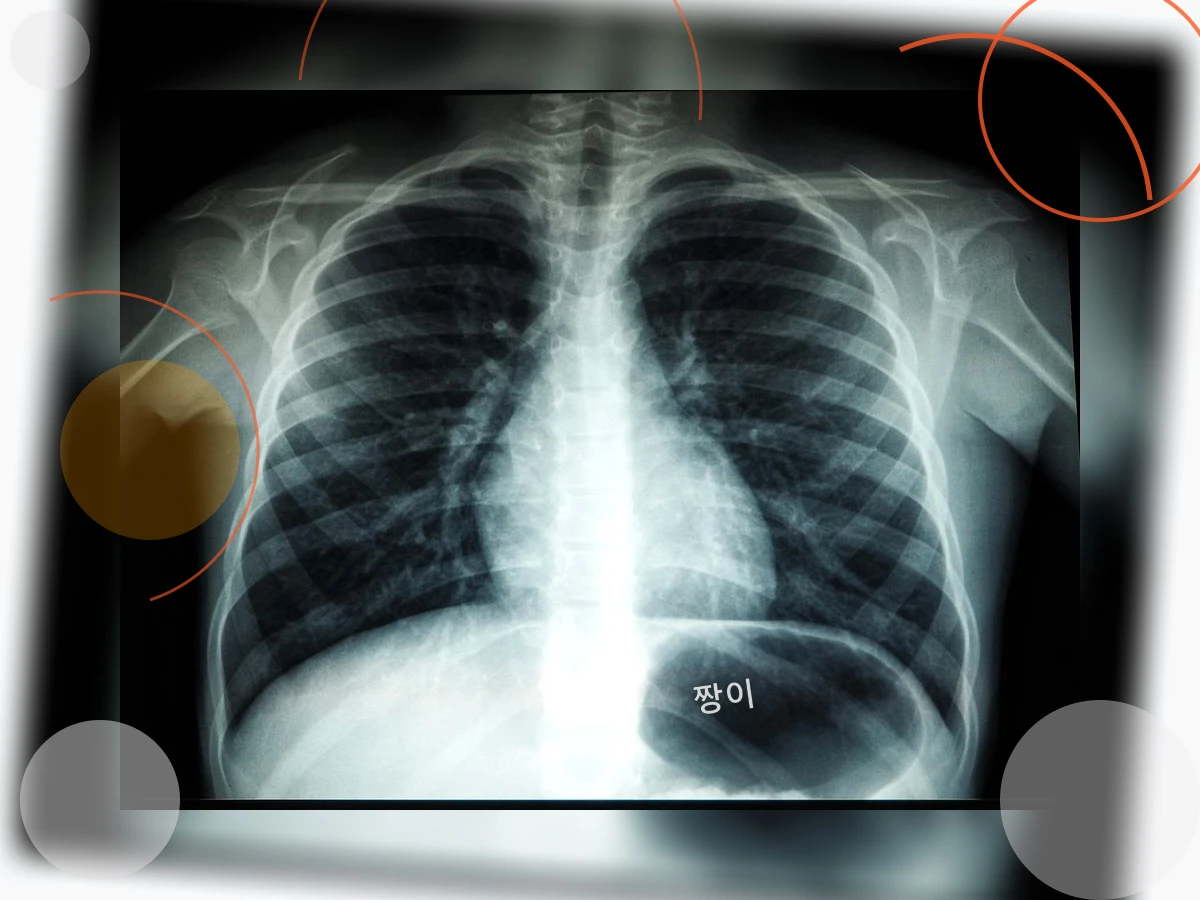

예를 들어, 감기에 걸린 후에도 기침이 2주 이상 지속된다면 기관지염을 의심해 볼 수 있습니다. 또한, 흡연자라면 만성 폐쇄성 폐질환(COPD)의 가능성을 배제할 수 없습니다. 알레르기성 비염이나 천식이 있는 경우에도 기침과 가래가 잦을 수 있으며, 심지어 역류성 식도염 때문에 기침이 유발되는 경우도 있습니다.

따라서 잦은 기침과 가래가 있다면, 그 원인을 정확히 파악하는 것이 중요합니다. 단순히 약국에서 기침약을 사 먹는 것으로는 근본적인 해결이 어렵습니다. 병원을 방문하여 전문의와 상담하고, 필요한 검사를 통해 정확한 진단을 받는 것이 우선입니다.